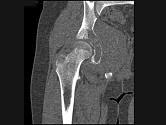

问题 男,15岁,右髋部疼痛、红肿,有压痛,皮温增高,结合图像,最可能的诊断是?(?)

选项 A.骨肉瘤 B.急性骨髓炎 C.尤文肉瘤 D.转移性神经母细胞瘤 E.骨结核

答案 C